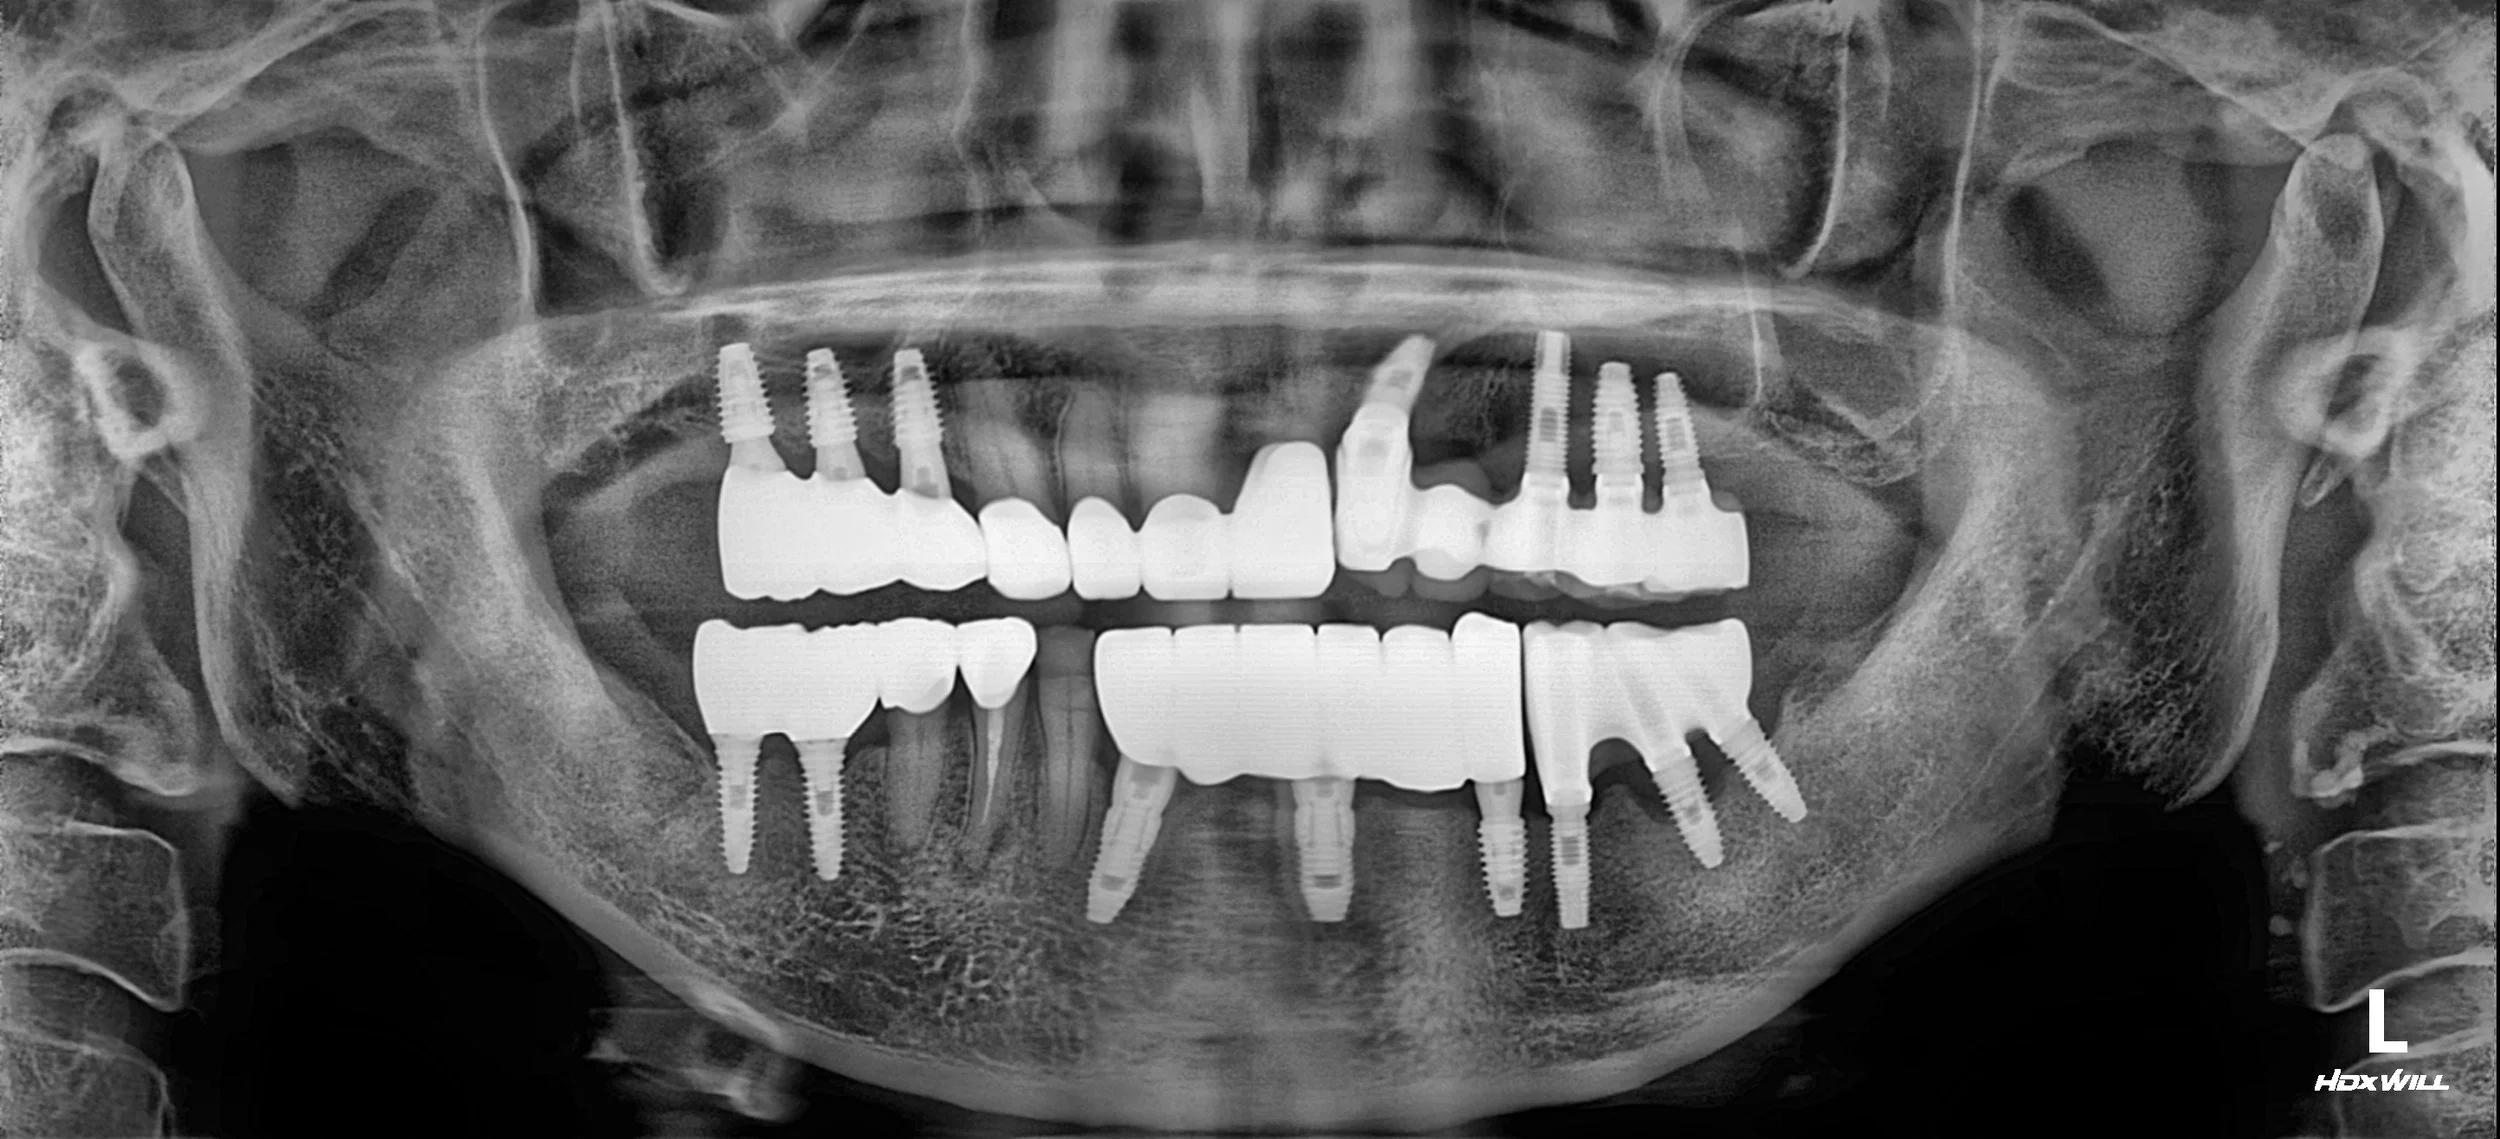

INTRA ORAL - AFTER